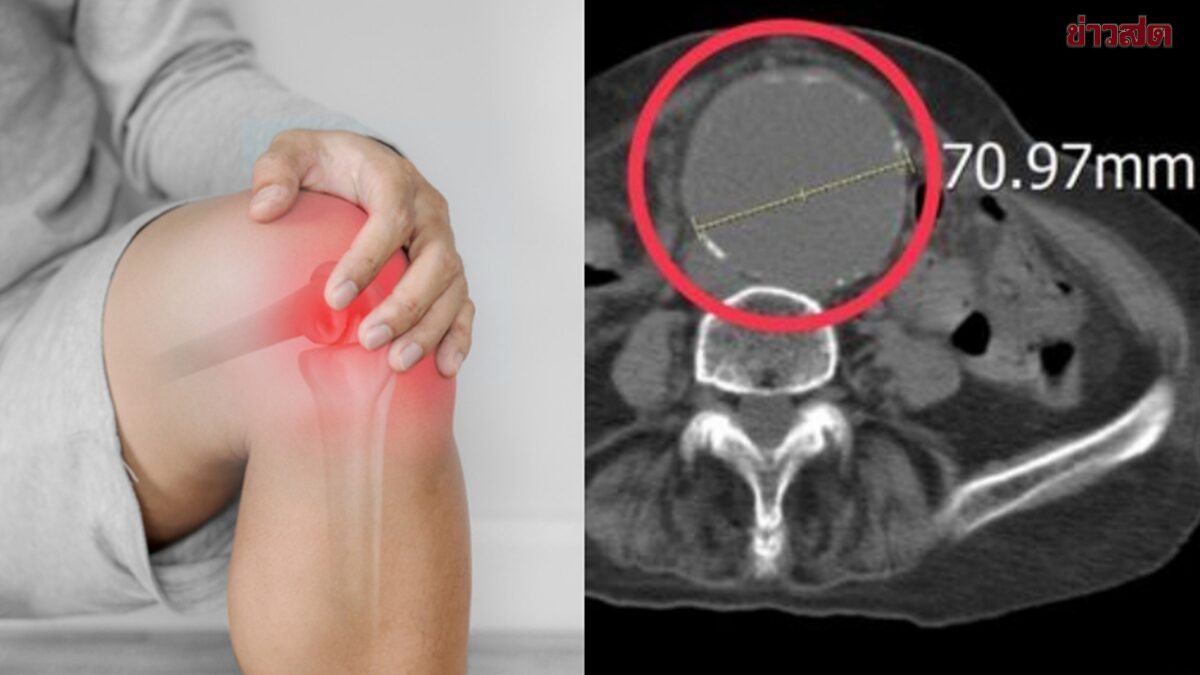

หญิงไต้หวันปวดขา-ปวดเอว ที่แท้เป็น “หลอดเลือดโป่งพองขนาดใหญ่” แพทย์เตือน หากมีอาการปวด 4 แบบนี้ต้องระวัง หญิงรายหนึ่งในเมืองไทจงมีอาการปวดเมื่อยที่ขาซ้ายอย่างรุนแรง จึงเดินทางไปห้องฉุกเฉิน เมื่อทำการตรวจอัลตราซาวด์กลับพบว่า เธอมีหลอดเลือดแดงใหญ่ในช่องท้องโป่งพองเป็นก้อนขนาดใหญ่ถึง 7 เซนติเมตร หลังได้รับการผ่าตัดฉุกเฉิน ปัจจุบันอาการดีขึ้นและสามารถออกจากโรงพยาบาลได้แล้ว นพ.ซุนซิ่วเจิ้ง แพทย์ประจำห้องฉุกเฉินของโรงพยาบาลผิงเติ่งเฉิงชิง ระบุว่า ภาวะหลอดเลือดแดงใหญ่ในช่องท้องโป่งพอง (Abdominal Aortic Aneurysm) มักถูกเรียกว่า “ฆาตกรเงียบ” เนื่องจากผู้ป่วยบางรายอาจมีเพียงอาการปวดท้อง ปวดเอว ปวดหลัง หรือปวดขา ซึ่งมักถูกเข้าใจผิดว่าเป็นอาการปวดกล้ามเนื้อหรือปัญหาข้อต่อ แต่หากหลอดเลือดแตก จะมีอัตราการเสียชีวิตสูงมาก ผู้ป่วยรายนี้มีอายุ 86 ปี ขณะเข้ารับการรักษาที่ห้องฉุกเฉิน ได้บอกแพทย์ซ้ำ ๆ ว่ามีอาการปวดเมื่อยที่ขาซ้ายและรู้สึกไม่สบายบริเวณเอว โดยไม่มีประวัติการบาดเจ็บชัดเจน และมีระดับความปวดสูงถึง 8 – 10 คะแนน จากการตรวจด้วยเครื่องมือวินิจฉัยแบบทันที พบว่าหลอดเลือดแดงใหญ่ในช่องท้องมีการขยายตัวอย่างชัดเจน โดยมีเส้นผ่านศูนย์กลางเกิน 7 เซนติเมตร จึงได้ทำการตรวจเอกซเรย์คอมพิวเตอร์ (CT scan) เพิ่มเติม และยืนยันว่าเป็นภาวะหลอดเลือดโป่งพองขนาดใหญ่ นพ.ซุนซิ่วเจิ้งอธิบายว่า […]